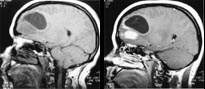

Svulster kan opptre i alle aldre og med høyst forskjellig intrakranial lokalisasjon. Ved bruk av flere ulike pulssekvenser og snittplan kan MR fremstille en svulst bedre enn andre tilgjengelige metoder. MR er således bedre enn CT til å identifisere og nøyaktig lokalisere svulsten. Samtidig forbedres fremstillingen av tumormorfologien, effekten på omkringliggende hjernevev og store intrakraniale blodkar. MR identifiserer solide og cystiske tumorkomponenter så vel som kontrastmiddeloppladende eller ikke-oppladende svulstvev (fig 1, 2 ). Ofte finner vi ved MR hjernemetastaser som ikke er synlige selv med en god CT-undersøkelse. Disse egenskapene ved MR har derfor kunnet gi vesentlig informasjon med henblikk på valg av terapi.

MR-teknikken har hatt stor betydning for barn med medfødte misdannelser (21). Spesielt gjelder det barn med myelomeningocele og migrasjonforstyrrelser i hjernen. I moderne behandling av hydrocephalus er de nye MR-teknikkene av stor betydning både før og etter nevrokirurgiske inngrep. Det er gunstig at det ved MR-diagnostikken ikke brukes ioniserende røntgenstråler. Disse barna ville ellers måtte utsettes for relativt store stråledoser gjennom et langt liv med CT-kontroller (22).